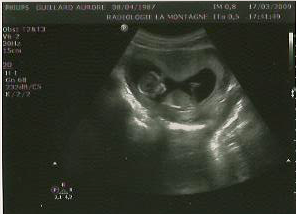

la cignogne m’a fait écouter le coeur du petit être vivant dans mon ventre, 🙂 c’est toujours aussi cool à entendre

la taille de la nuque du petit est de 1,3 et c’est au dessus de 3 qu’il faut s’inquièté… donc on est largement bon, mais une vérification n’est pas de trop.